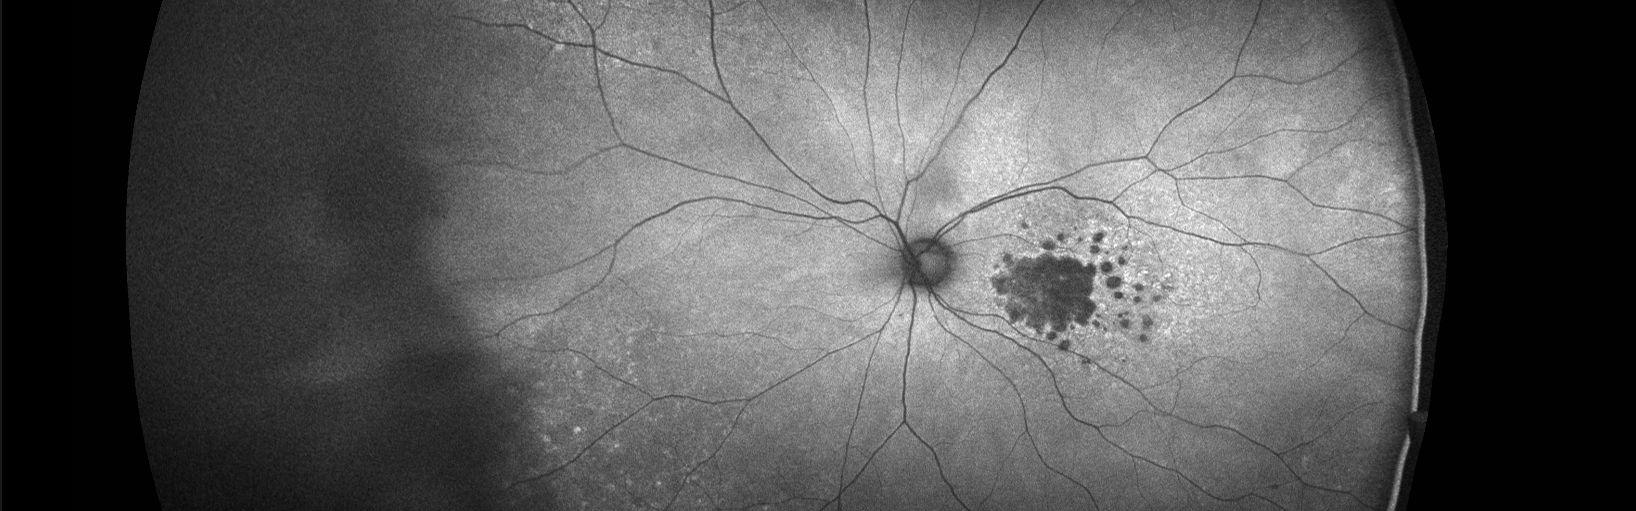

Research on Retinal Diseases

Our lab focuses on the genetic, epidemiological, and behavioral factors affecting macular degeneration and macular dystrophies and finding new therapies. We aim to identify the causes, prevention methods, and treatments for these diseases.

Our studies provide insights into why the diseases occur in some people and not others, why they progress to advanced stages amongst those affected, and how to prevent or delay its progression to reduce visual loss.